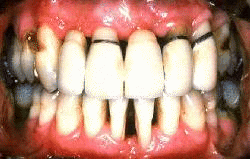

Mujer de 45 años de edad con la enfermedad periodontal severa antes del tratamiento. Los gingiva exhibe un color rojo intenso, hay bolsas profundas y sangrante al sondaje suave. El tratamiento consistió en gingivectomía, raspado y alisado radicular en los dientes superiores y solo raspado y alisado radicular en los inferiores. El incisivo lateral derecho superior y el central izquierdo inferior fueron extraídos por ser irrecuperables.